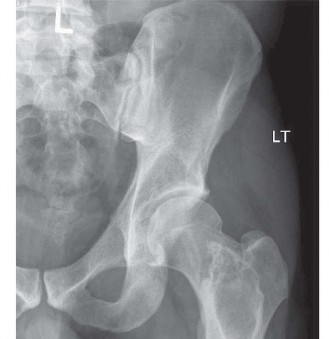

Initial plain radiographs of the left hip were obtained upon presentation. The anteroposterior (AP) and lateral views of the left hip demonstrated a comminuted, subtrochanteric fracture of the left femur. The fracture pattern involved significant cortical destruction and a large lytic lesion extending proximally into the intertrochanteric region and distally into the subtrochanteric area. The margins of the lytic lesion appeared ill-defined in several areas, raising strong suspicion for a neoplastic process. There was no evidence of periosteal reaction or overt sclerotic changes commonly associated with benign lesions or healing fractures.

This uncoupling results in aggressive osteolysis, presenting radiographically as punched-out lytic lesions, diffuse osteopenia, and ultimately, pathological fractures. The subtrochanteric region of the femur is particularly susceptible to these catastrophic failures due to its unique biomechanical environment, where immense physiological loads are concentrated across areas of focal cortical destruction.

A critical diagnostic nuance in multiple myeloma lies in the utility—or rather, the lack thereof—of standard Technetium-99m methylene diphosphonate bone scintigraphy. Standard bone scans rely on osteoblastic activity and regional blood flow for radiotracer uptake. Because multiple myeloma pathologically suppresses osteoblast function while upregulating osteoclasts, pure lytic myeloma lesions frequently present as "cold" or false-negative on standard bone scintigraphy.